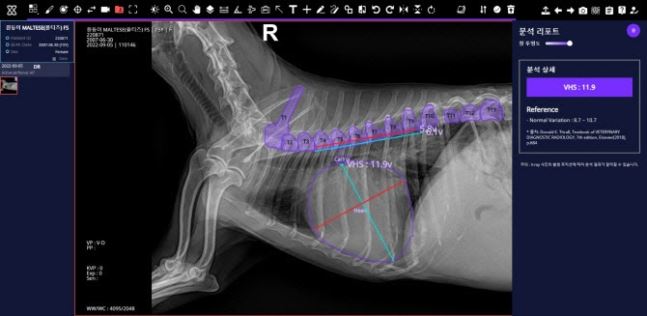

SK텔레콤 동물 의료 AI 서비스인 ‘엑스칼리버’를 통해 분석한 반려견의 VHS(심장크기측정) X-레이 사진. 이상 SK텔레콤 제공

'엑스칼리버'는 AI가 반려동물의 X-레이 사진을 분석해 진단 결과를 제공함으로써 수의사의 진료를 돕는 동물 의료 AI 서비스다. 병원에서 촬영한 반려견의 X-레이 사진을 엑스칼리버 전용 클라우드에 올리면 질환의 위치와 비정상 소견 등 분석 결과를 15초 내에 제공한다.